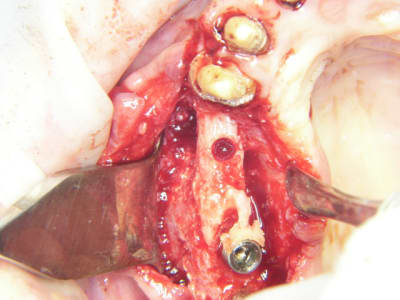

bon et bien ça c'est fait!

curetage (deux bonnes heures) dépose des deux vis d'ostéo et de l'implant en 16, nettoyage implant en 14/15 (axe un peu limite pour cause structure osseuse) et 17.

Vitalos

le greffon placé il y a 6 mois (grosse corticale) était dans le "vide" au niveau de 14, et il m'aurait fallu le piezzo éventuellement (il n'était pas installé, pour cette chir) pour "percer" la corticale sans pression, car à la fraise, je sentais le bloc plier, et nous avons préférés (avec le confrère) tenter un compromis pour la prothèse qui ne sera pas catastrophique et devrait permettre à la patient (qui a déjà subie 2 greffes, menton et ramique, avec un souvenir sympa du menton d'ailleurs)d'avoir une reconstruction fixe.

je ne sais pas si le vitalos permettra de rattraper ce cas là, mais vu tous les soucis que nous avons rencontrés pour le nettoyage (biooss infiltré dans la muqueuse de partout, j'ai du "virer" 60% du périoste et honnêtement je ne savais pas trop comment faire un "abri" de reconstruction pour l'os et l"environnement tissulaire, de façon simple.

photos montrant le hiatus greffe/os et pose avec vitalos à la fin